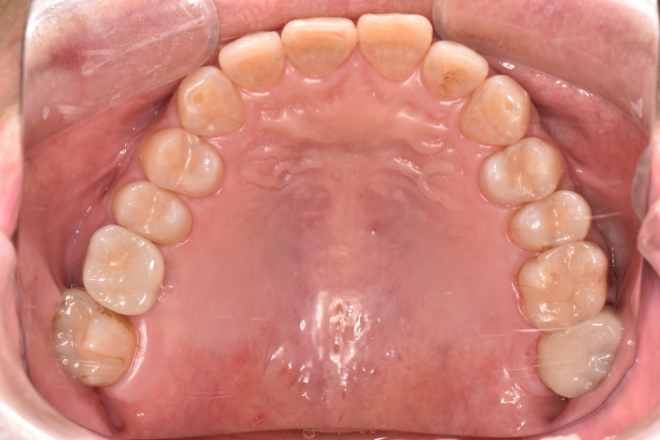

| 備考 | 右上の欠損部へのインプラントを希望で来院されました。 左下のブリッジの下にものが挟まりやすいとのことでブリッジ部分もインプラント埋入を希望されました。口腔内の銀歯も全て綺麗にやりかえたいとのことで、ダイレクトボンディングやセラミックインレーやジルコニアクラウンでやりかえていきました。 右上6番のインプラント埋入時にはソケットリフトで骨造成を行なっています。 見た目だけではなく噛みやすくなりとても満足されています。現在はエアフローのクリーニングやホワイトニングで通院されています。 |